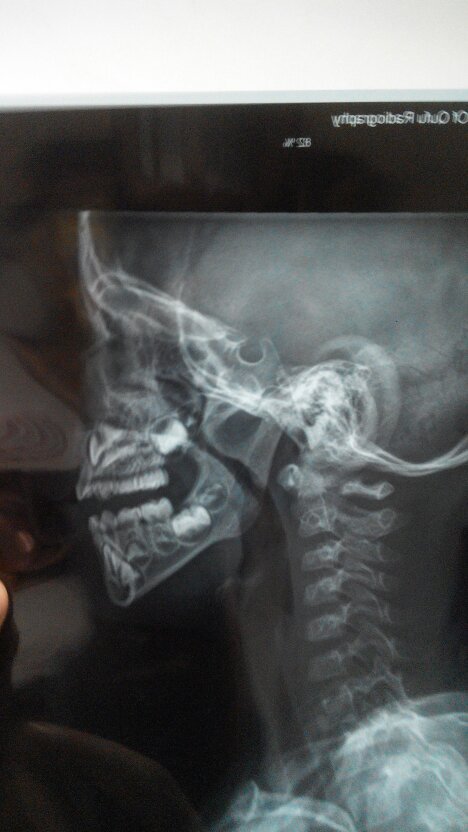

孩子平时呼吸不通畅,晚上睡眠质量不行,有事打呼噜,平躺憋气2-3秒,翻身时憋气5秒。在县医院检查医生没有给确切答复。只是说孩子太小,需要去市医院检查。检查结果上面也没有说明大小,只是拍了个片子。现在心里没底,不知道到底严重不严重。

如果是儿童,应该到大的儿童医院五官科看,拍的应该是鼻腔里面的彩色图片,不是这种片。如果这样下去对健康影响很大的。